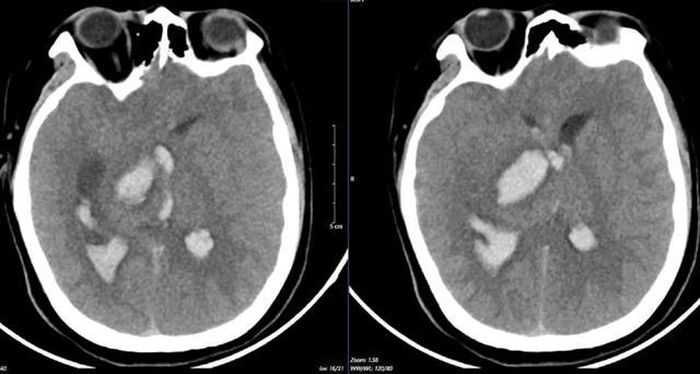

Sau khi thăm khám và kết quả chụp lại phim MSCT mạch não cho thấy tình trạng chảy máu não do vỡ khối dị dạng mạch máu não. Bệnh nhân biến chứng giãn não thất cấp, rối loạn thân nhiệt, sốt cao liên tục 39 - 40 độ C.

Hình ảnh chụp phim MSCT cho thấy tình trạng chảy máu não do vỡ khối dị dạng.

Kết quả chụp phim MSCT mạch não: Hình ảnh chảy máu não thùy đỉnh chẩm bên trái và não thất - phù não lan tỏa do vỡ ổ dị dạng AVM thùy đỉnh chẩm trái (điểm Spetzler- Martin 3 điểm). Sau đó, người bệnh được phẫu thuật hút khối máu tụ và lấy ổ dị dạng mạch não. Hiện, bệnh nhân vẫn đang điều trị tích cực tại khoa Hồi sức Ngoại, tiên lượng khả năng hồi phục hạn chế.